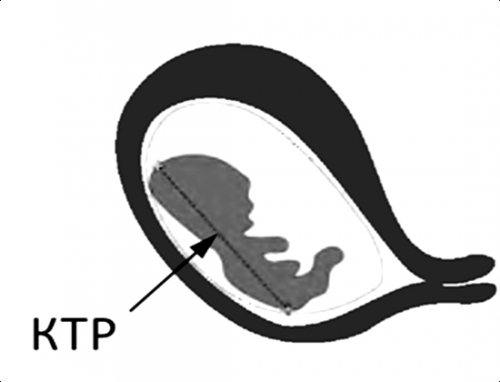

- КТР.

Куприка-тім'яної розмір - що за показник?

КТР, або куприка-тім'яної розмір плоду, це особливий показник, який визначається на УЗД. Він настільки важливий, що з його допомогою визначають, повноцінно чи проходить розвиток плода. При виявленні незначних відхилень призначають відповідне коригуючий лікування для успішного завершення вагітності.

КТР визначає точний термін вагітності, адже відповідно до терміну з моменту зачаття плід безперервно зростає. Кожен день показник КТР збільшується!

Давайте порівняємо показники КТР протягом усього 10-го тижня вагітності:

10 й тиждень, КТР плода